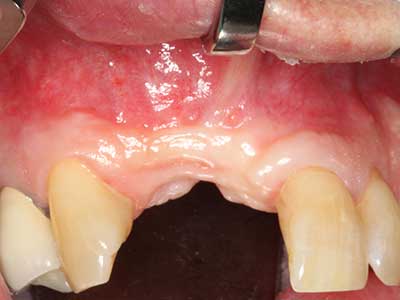

Bone tissue is not simply a mineral structure but also contains a substantial proportion of collagen fibres. This means it not only has good compressive strength but also a degree of flexibility, which can be taken advantage of when performing bone augmentations. In the classical expansion procedure using bone splitting, the atrophied alveolar ridge is split longitudinally and carefully expanded after reaching an adequate osteotomy depth (Fig. 13-16), ideally without substantial removal of the periosteum (Brugnami, Caiazzo et al. 2014, Stricker, Fleiner et al. 2014). Screw and plate systems with increasing expansion distance have proven effective in separating the two bone lamellae while remaining below the fracture threshold. In general, residual bone widths of at least 3–4 mm are required (Chiapasco, Zaniboni et al. 2006) to guarantee adequate flexibility and sufficient bone coverage of the future implants. If necessary, a vertical relief osteotomy on one or both sides can improve flexibility. A combination with additional augmentation techniques, particularly on the buccal side, has been described as an alternative to the classical technique.

The splitting procedure is particularly atraumatic and there is no significant loss of dimension when using piezosaws, and there are no significant differences between implants in split jaws and implants in an alveolar ridge without a bone deficit (Chiapasco, Zaniboni et al. 2006, Danza, Guidi et al. 2009). However, sufficient continuous irrigation is essential, particularly with locally restricted and deep splitting to prevent thermal stress in the apical osteotomy regions.